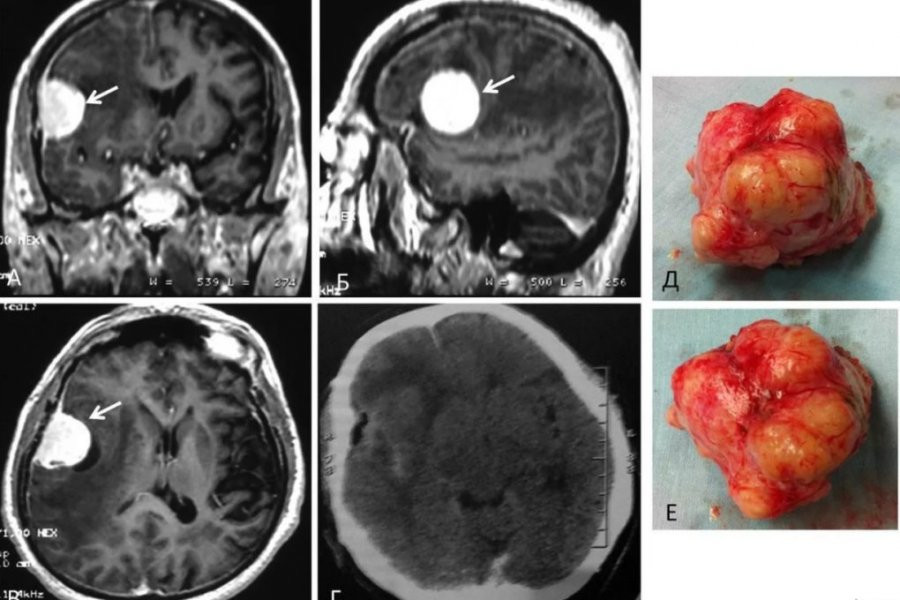

Обследования показало, что у Хэмптона образовалась в мозге злокачественная опухоль - глиобластома, которая является агрессивной формой рака. Это заболевание и оказало влияние на его характер. Мужчине была проведена операция, и его поведение вернулось в норму. Сейчас Хэмптон проходит химиотерапию.